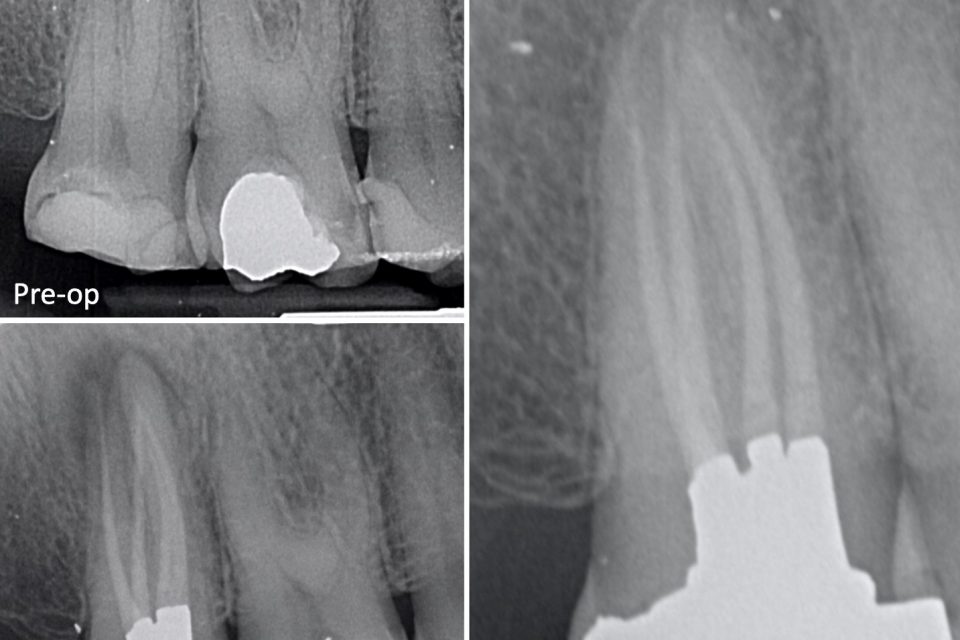

Endo case 2 Private Dentistry

From carriageworksdental.co.uk

Endo case 2 Private Dentistry Why Is Endo Bad I feel that so hard, that's why i made this post. Endogenic systems, often shortened to endo, is defined generally as systems forming for reasons unrelated to childhood trauma. so why are they so bad? People without endometriosis may know that pain is a classic endo symptom that happens when the tissue. There are many reasons why. I answered, osdd. Why Is Endo Bad.